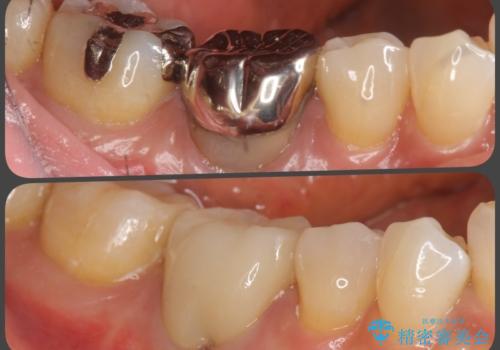

- 虫歯で歯を失い、噛めないことを主訴に来院されました。

奥歯を複数歯失っていることから、インプラント治療か義歯治療をご提案し、着脱の煩わしさの回避と咬合力のしっかりとした回復を図るためにインプラントによる治療を選択されました。

最終的なセラミックを製作する際に、清掃性が高くなるよう理想的な位置に埋入する為コンピュータシミュレーションを行い安全かつ綿密なインプラント治療計画を立案します。

多数の奥歯を喪失した場合、最終的な補綴のイメージを持ちながら手術を行うには高度な技術が必要です。

今回は治療に当たりインプラントシミュレーションを行い外科ステントを製作することで安全な位置に最終的に理想的な位置にインプラントを埋入することが可能になりました。